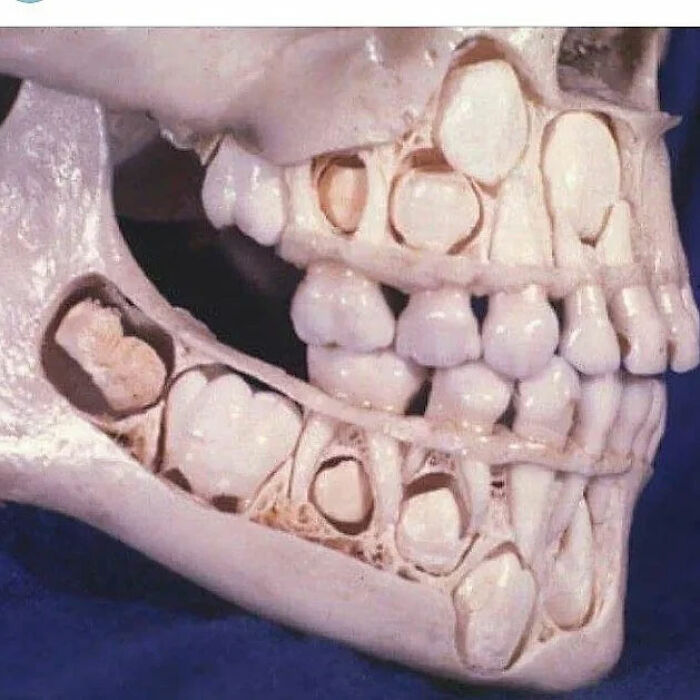

Child Mouth Before Loosing Their Teeth

After seeing this for the first time some years ago, I've not been able to see little kids as being cute since.

They Surely Removed All His Teeth! Ostectomy Of Maxillary And Mandibular Alveolar Ridge, With Removal Of Entire Dentition - In Preparation For Full-Mouth Implants